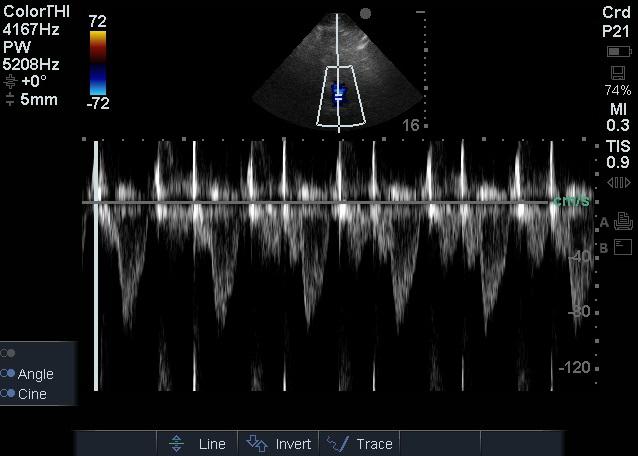

1.2 方法患者入院24 h内完成心脏超声检查。患者左侧卧位,以能显示心尖四腔心切面及五腔心切面为准,以美国Sonosite公司Edge超声诊断系统相控阵探头经心尖对患者二尖瓣、LVOT进行评估,彩色多普勒显示血流束,脉冲型频谱多普勒测量二尖瓣E峰流速及LVOT峰值流速(图 1~2),连续显示多个呼吸周期,选取呼吸周期内血流速变化规律波形,测量血流速最大值及最小值,重复以上过程,每个测量部位血流速共测量三组最大值及最小值,然后计算平均数。二尖瓣E峰流速呼吸变异度=(二尖瓣E峰流速最大值-二尖瓣E峰流速最小值)/[(二尖瓣E峰流速最大值+二尖瓣E峰流速最小值)/2],LVOT峰值流速呼吸变异度=(LVOT峰值流速最大值-LVOT峰值流速最小值)/[(LVOT峰值流速最大值+LVOT峰值流速最小值)/2][1]。

| 图 1 LVOT频谱多普勒检查 Figure 1 LVOT Doppler examination |